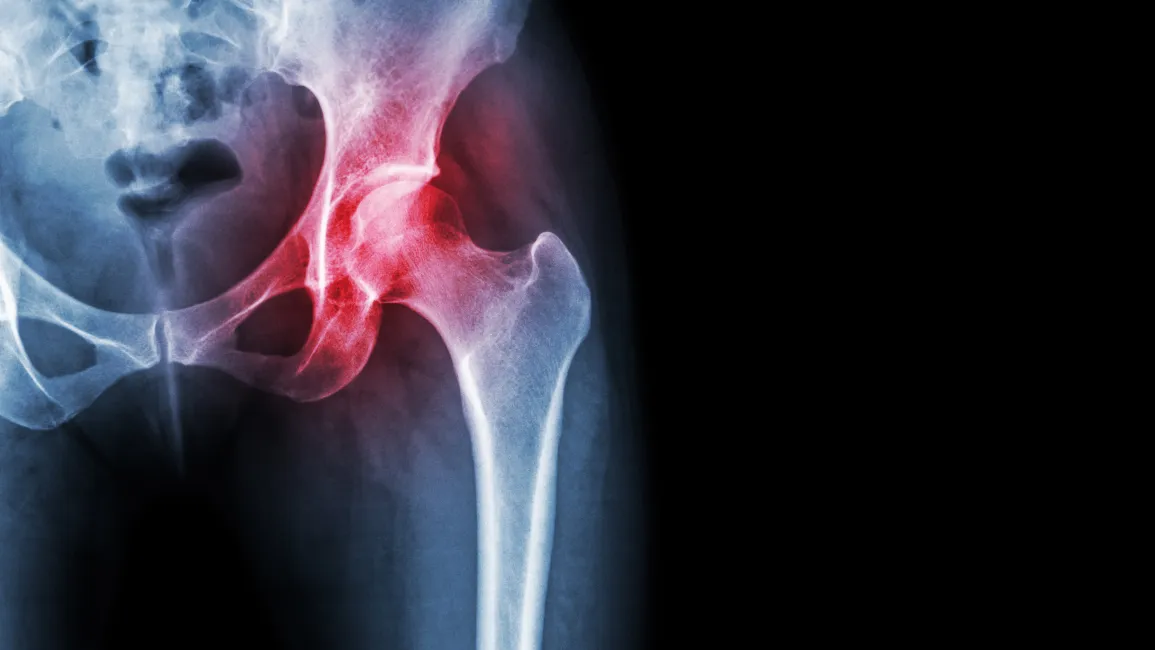

Hip pain does not always have to end in joint replacement surgery.

When you suffer from severe hip pain, degenerative arthritis in your hips, or even facing hip replacement surgery, the first choice should be Balance Wellspace Integrative Medicine in Roanoke, Virginia.

We are a team of results-driven healthcare providers who specialize in the treatment of joint pain, osteoarthritis, and the most severe degenerative arthritis conditions. Using the most innovative regenerative medicine techniques, we offer both relief and often an alternative to total joint replacement surgery for many patients suffering from hip pain in Roanoke, VA.

If prolonged sitting, standing, walking, or even lying on your side at night causes you severe hip pain, make an appointment immediately! If you have been diagnosed with bursitis or are told your hip is bone-on-bone, make an appointment. Our Roanoke, Virginia integrative team will evaluate your symptoms and x-rays to provide the best recommendations for the optimal treatment and fastest relief possible.